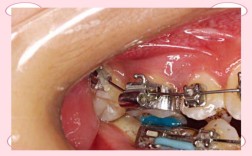

正畸带环(也称为带环或颊面管带环)既可以用于上牙,也可以用于下牙,具体取决于牙齿的位置和矫正方案的需求,以下是更详细的解释:主要作用位置:磨牙(尤其是第一磨牙)带环最常用于上下颌的第一恒磨牙(俗称“六龄齿”),这是因为磨牙牙冠较大,能提供足...